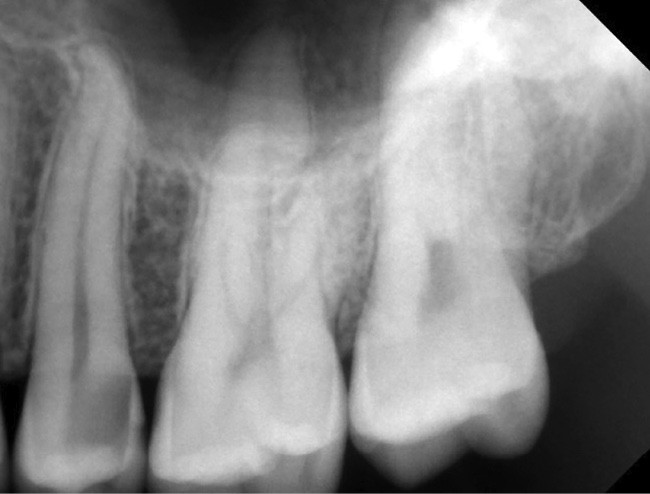

Si l’étude de Peters [18] nous montre que l’instrumentation laisse 35 % du volume canalaire non instrumenté, Ricucci et Siqueira montrent que la préparation physico-chimique n’élimine que partiellement les tissus nécrotiques à l’entrée des canaux latéraux, des isthmes et des ramifications apicales, en laissant des tissus enflammés et infectés, en association avec des lésions apicales [29] (fig. 4 et 5).

Fig. 4 – Coupe d’une racine mésiale de molaire mandibulaire avec deux canaux traités. Coupe à 3 mm de l’apex, coloration Brown et Brenn, technique modifiée par Taylor. Ces images montrent un isthme étroit avec une infection bactérienne, ce qui prouve l’importance de désinfecter et d’inclure l’isthme dans les traitements conventionnels et dans les rétropréparations apicales en chirurgie endodontique.